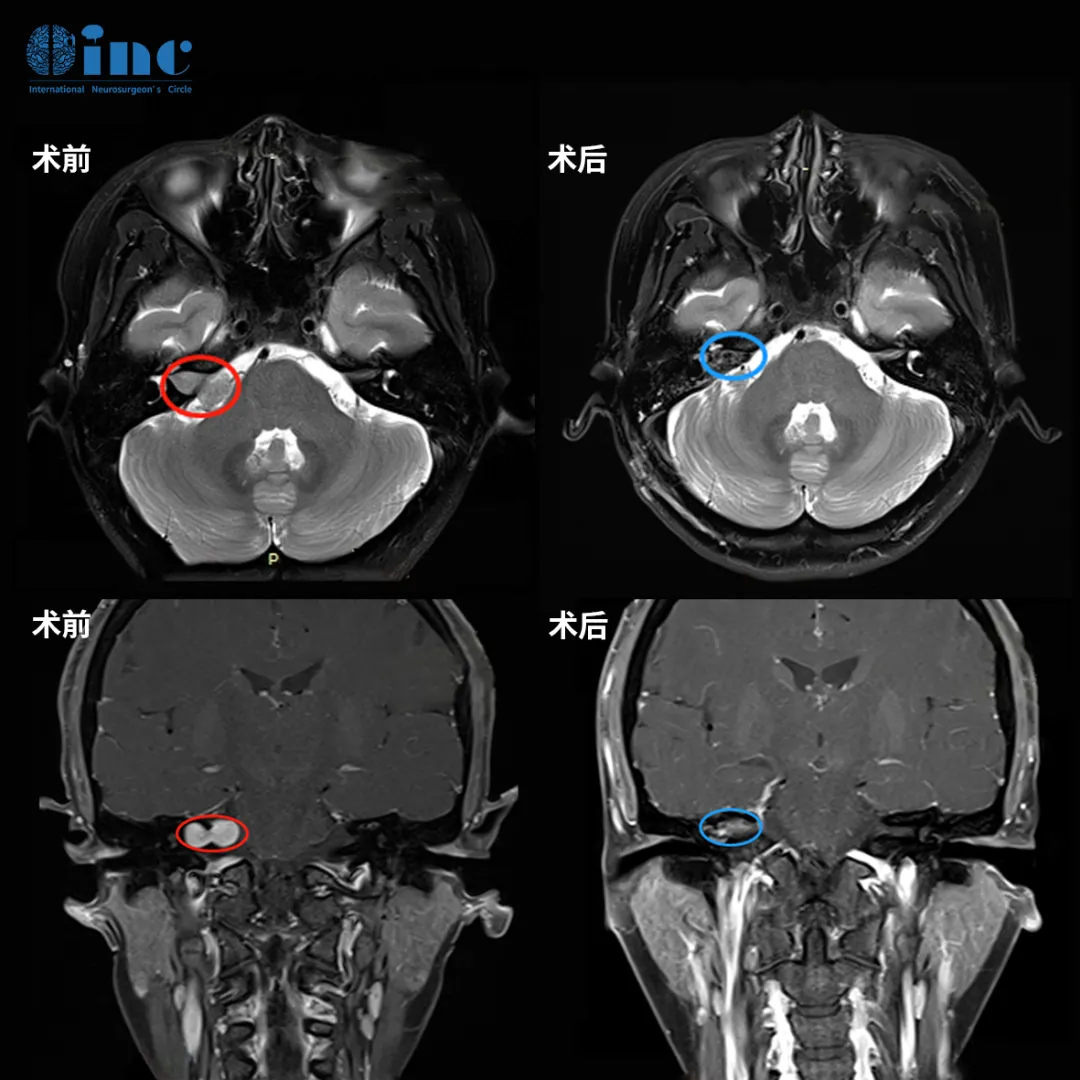

想到这些手术失败的后果,姜女士更加坚定了治疗思路:“手术要么不做,做就要做好,第一次手术尽量全切,而且一定不能面瘫”。因此,她找到INC巴教授为她全切了肿瘤,还保住了面神经。

3、“太好了,我没有面瘫!”

她醒来的第一句话就是:“太好了,我真的没有面瘫!”,术后第2天她就转出了ICU回到普通病房,教授查房时会耐心地解答问题,在医护人员的精心照料下,术后1周她就出院了。